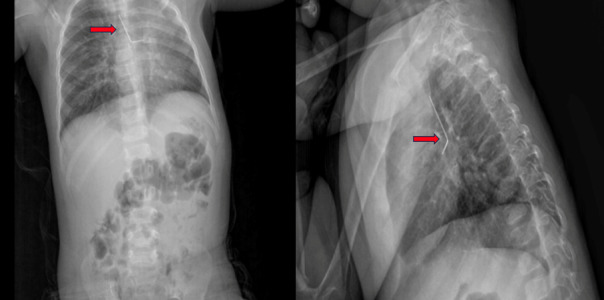

Case description: A 19-month-old female was admitted to another hospital with a persistent cough complaint. In X-ray left hijab pin has been detected. The patient underwent a succesfull removal with rigid broncoscopy (RB). A total of 71 patients included this meta analysis. The thoracotomy rate was 8%. The bleeding rate was reported as 1.4%. The reoperation rate was reported as 9.8%. The postoperative intubation rate was reported as 1.4%. The calculated complication rate was found to be 5.6% based on the existing literature. The postoperative hemoptysis incidence was calculated as 0%. Mortality was not reported across any included studies. However, the mortality incidence was calculated as 0% based on included studies.